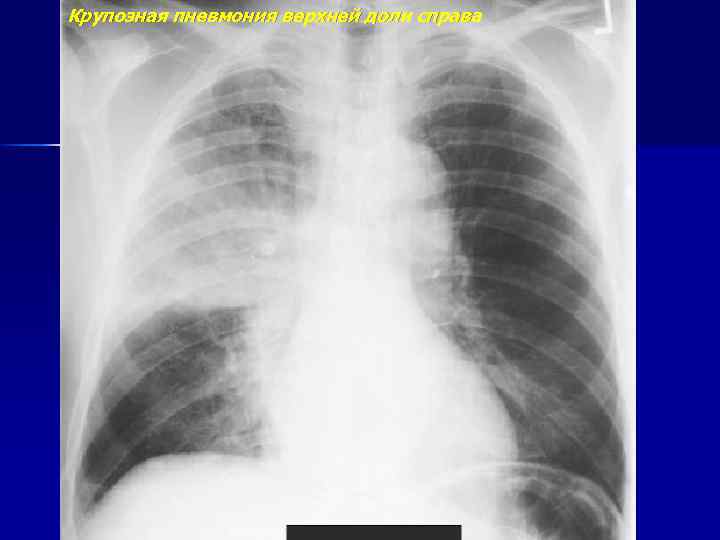

Крупозная пневмония верхней доли справа